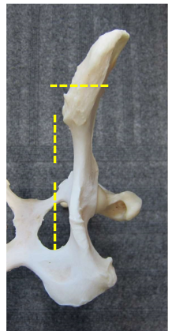

What is the theory of the triple pelvic osteotomy?

Acetabular segment rotated laterally to capture femoral head –> stabilise hip –> clinical improvement and reduced DJD

Theoretically, degree of rotation determined from Ortolani angles (20, 30, 40 degree plates)

Bilateral surgery if appropriate -staged